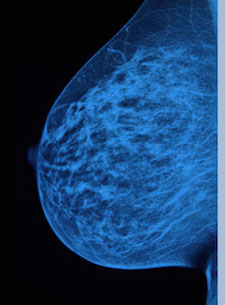

<a href="http://www.shutterstock.com/pic-291683438/stock-photo-doctor-with-mammography.html?src=pd-same_artist-292061510-oPKaVtph3CQ8kAC1zRyd2A-6"> Guschenkova</a>/Shutterstock

In a major shift following years of mounting evidence that women may be receiving too many mammograms, the American Cancer Society on Tuesday released new guidelines recommending that women start getting the tests later, at age 45, and only every other year.